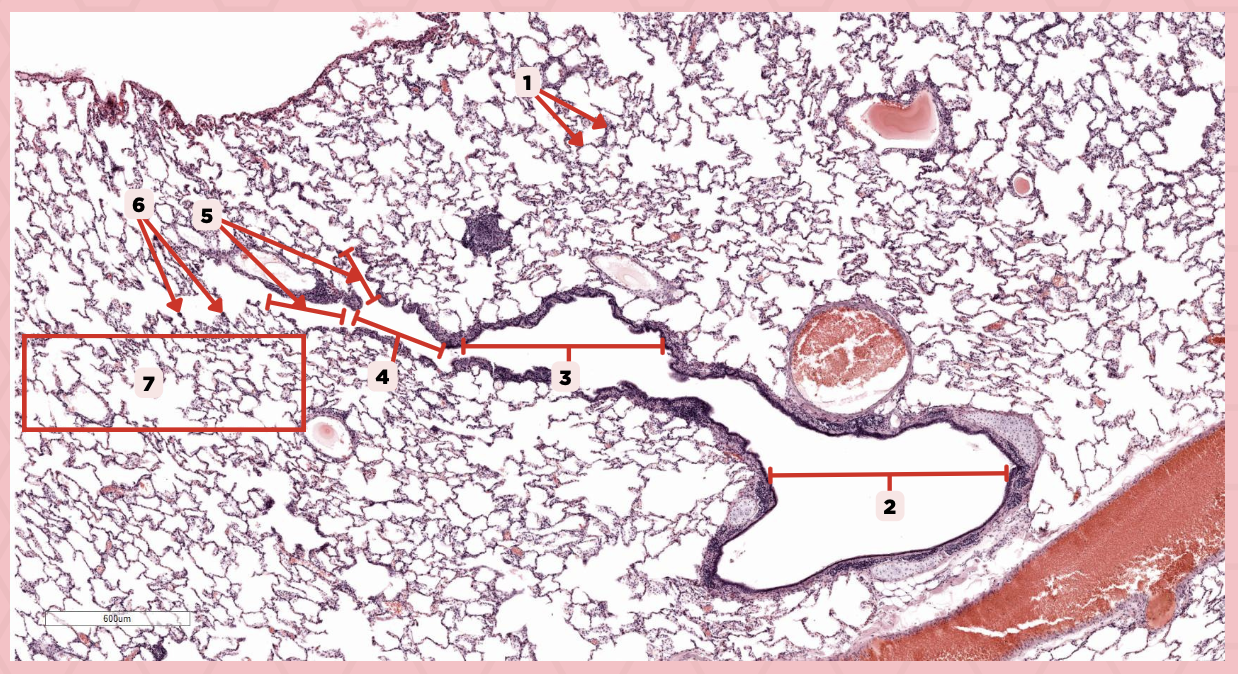

Lumens and Interalveolar septa

Name the irregular spaces and the fine threads of tissue that separate them.

Visceral pleura

Identify the structure labeled as 1.

Alveoli

Identify the structure labeled as 2.

Bigger and smaller intrapulmonary bronchi

What are the two types of intrapulmonary bronchi?

Pseudostratified epithelium (bigger bronchioles), Simple columnar or cuboidal (smaller)

What are the types of epithelium in No. 3?

Interalveolar septa

Identify the structure labeled as 1.

Intrapulmonary bronchi

Identify the structure labeled as 2.

Bronchiole

Identify the structure labeled as 3.

Terminal bronchiole

Identify the structure labeled as 4.

Respiratory bronchiole

Identify the structure labeled as 5.

Alveolar ducts

Identify the structure labeled as 6.

Alveolar sacs

Identify the structure labeled as 7.